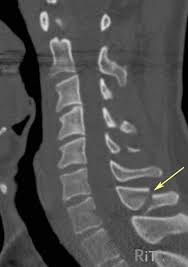

A transverse process fracture at the level of l5 is a surrogate marker of vertical instability of the pelvic fracture due to the attachment of the iliolumbar ligaments. Possible causes, signs and symptoms, standard treatment options and means of care and support. Transverse processes are used as lever arms by the deep spinal muscles to maintain posture and to induce rotation and lateral bending. It may occur as an avulsion fracture due to strong contracture of the muscles. Although the fracture is not associated with spinal cord damage and neurological deficits, the extreme force of the injury can cause visceral injuries and internal hemorrhage. The presence of other injuries might also be assessed due to the level of force needed to break the transverse process. In 78% of transverse process fractures, ct scanning showed that the fracture extended into the transverse foramen. Transverse process fractures caused by stress are likely under detected since even an acute transverse process fracture requires a high index of suspicion to be correctly identified(4,7). Here is an example of a patient with a benign looking transverse process fracture with an associated significant injury to the back. Transverse process fracture you have fractured a transverse process. Thoracic transverse process fractures (ttpfs) are injuries that go unnoticed during traditional autopsies, as demonstrated by a lack of medicolegal publications regarding ttpfs. We retrospectively reviewed the reports of lumbar spine and abdominopelvic ct scans from 2017 and 2018 to classify the types of spine fractures, their mechanism of injury, treatment and. Up to 60% of lumbar transverse process fractures identified on ct will be missed on plain radiographs.

The transverse foramen is an opening on each of the transverse processes of the cervical spine which gives passage to the vertebral artery and vein and a sympathetic nerve plexus. There are two transverse processes that extend off each vertebra in the details: Transverse process fractures are common sequelae of trauma, although they are considered a minor and stable lumbar spine fracture. Transverse processes are typically fractured in direct blows from athletics touch or impact from falls from bikes/motorbikes or by heights. However, postmortem computed tomography (pmct) has made detection of this type of injury easy. There are two transverse processes that extend off each vertebra in the spine, one on each side. A transverse process fracture is a break in 1 or more transverse process. In 78% of transverse process fractures, ct scanning showed that the fracture extended into the transverse foramen. A transverse process fracture is considered as a rare injury. A transverse process fracture is a break in 1 or more transverse process. What is a transverse process fracture? Transverse process fractures caused by stress are likely under detected since even an acute transverse process fracture requires a high index of suspicion to be correctly identified(4,7). If ct confirms isolated injury lateral flexion/extension views are indicated to rule out dynamic instability.

However, postmortem computed tomography (pmct) has made detection of this type of injury easy. There are two transverse processes that extend off each vertebra in the details: What is a transverse process fracture? It may occur as an avulsion fracture due to strong contracture of the muscles. It occurs as a result of sudden and extreme trauma. If ct confirms isolated injury lateral flexion/extension views are indicated to rule out dynamic instability. Vertebral angiography, performed in eight patients with fractures involving the transverse foramen, showed dissection or occlusion of the vertebral artery in seven (88%) instances. This part extends out from the side of the main body of the bone (called the vertebral body). A transverse process fracture at the level of l5 is a surrogate marker of vertical instability of the pelvic fracture due to the attachment of the iliolumbar ligaments. We retrospectively reviewed the reports of lumbar spine and abdominopelvic ct scans from 2017 and 2018 to classify the types of spine fractures, their mechanism of injury, treatment and. Up to 60% of lumbar transverse process fractures identified on ct will be missed on plain radiographs. In 78% of transverse process fractures, ct scanning showed that the fracture extended into the transverse foramen. Transverse process fractures identified on helical computed tomography (ct) scans without the presence of any other fracture or.